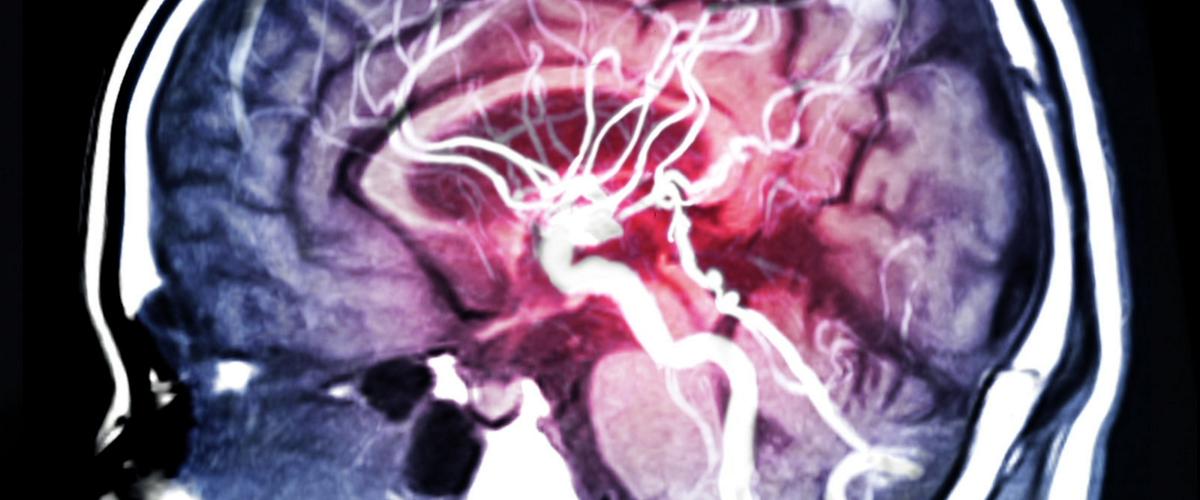

В основе методики лежит технология глубокого обучения, которая делает выводы, анализируя данные электроэцефалограммы. Алгоритм сравнивает состояние мозга пациента с информацией об электрической активности, предшествующей приступу.